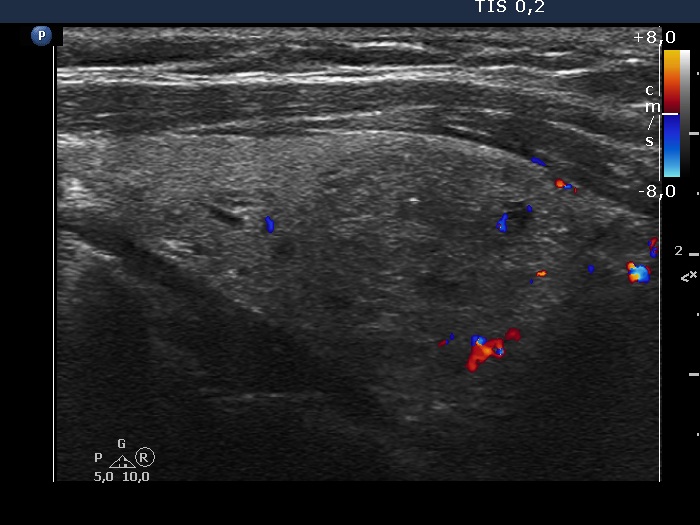

Study on 100 consecutive patients with thyroid nodule - case 067 (ultrasonographic picture 5)

Left lobe, longitudinal view, color Doppler mode. The nodule is almost avascular.